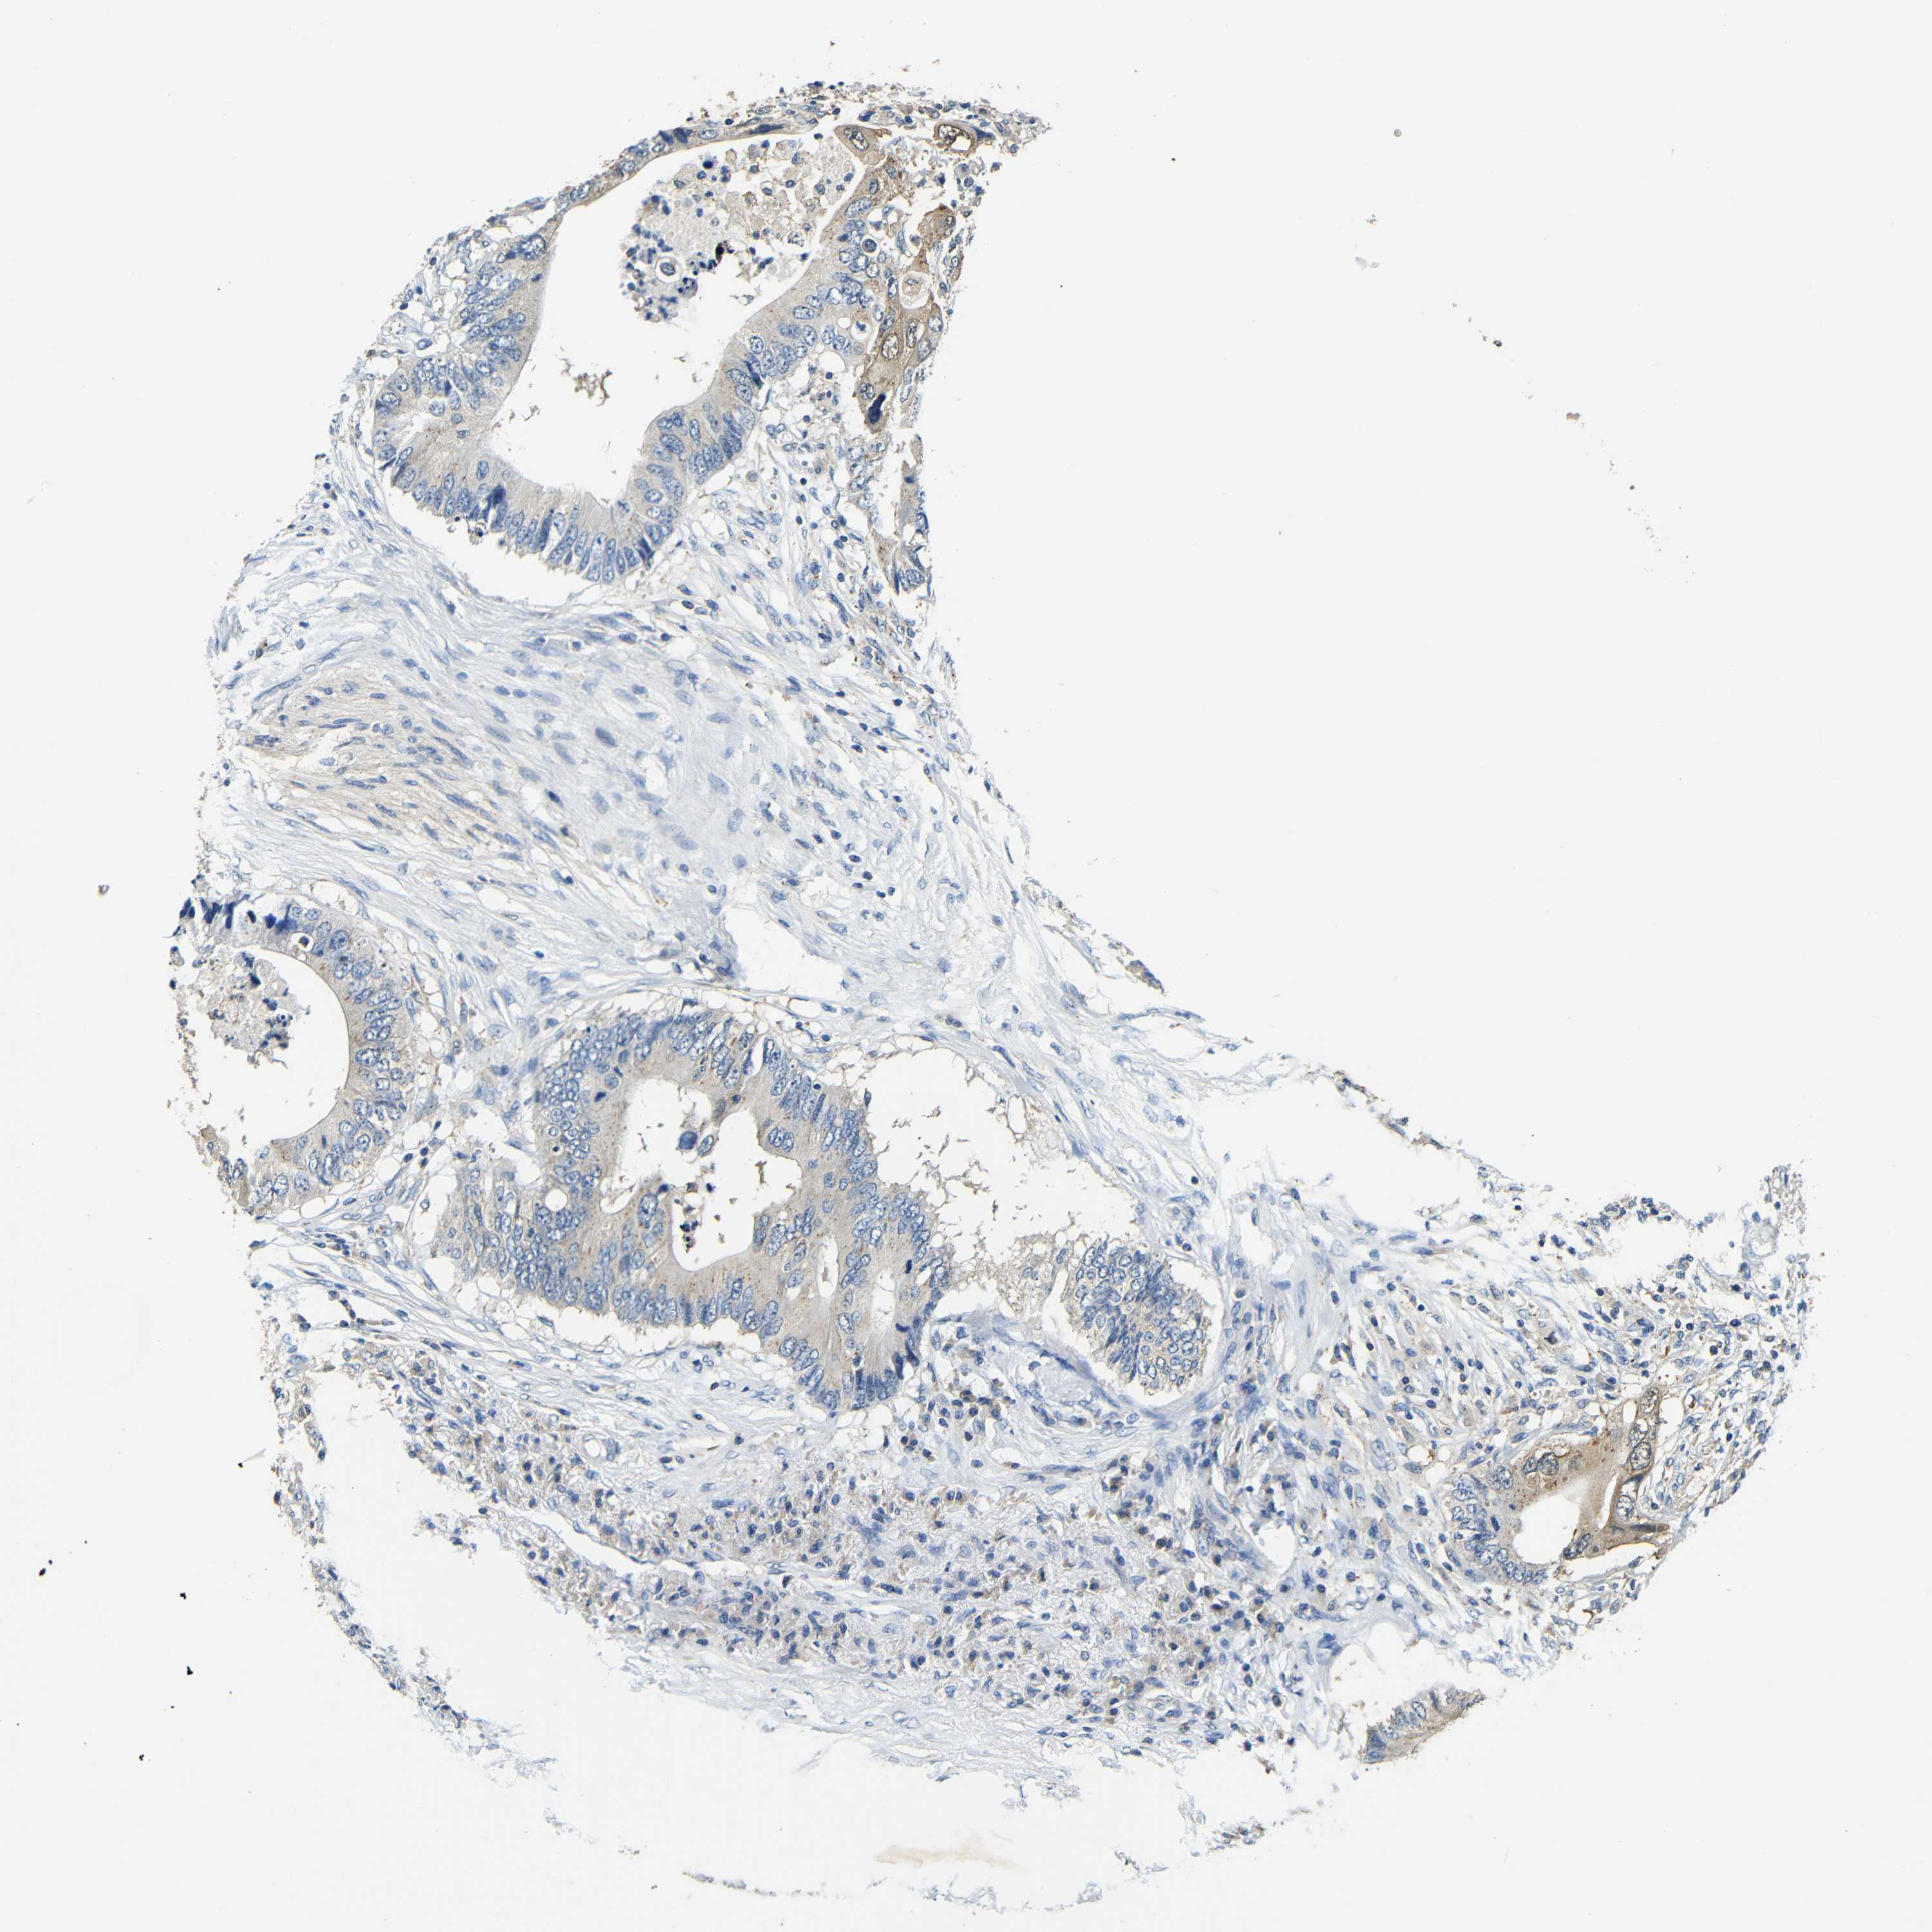

RECTUM ADENOCARCINOMA (TCGA) - Interactive survival scatter ploti

The Survival Scatter plot shows the clinical status (i.e. dead or alive) for all individuals in the patient cohort, based on the same data that underlies the corresponding Kaplan-Meier plots. Patients that are alive at last time for follow-up are shown in blue and patients who have died during the study are shown in red.

The x-axis shows the expression levels (FPKM) of the investigated gene in the tumor tissue at the time of diagnosis. The y-axis shows the follow-up time after diagnosis (years). Both axes are complimented with kernel density curves demonstrating the data density over the axes. The top density plot shows the expression levels (FPKM) distribution among dead (red) and alive patients (blue). The right density plot shows the data density of the survived years of dead patients with high and low expression levels respectively, stratified using the cutoff indicated by the vertical dashed line through the Survival Scatter plot. This cutoff is automatically defined based on the FPKM cutoff that minimizes the p-score. The cutoff can be changed by dragging the vertical line or by entering a cutoff value in the square labeled "Current cut-off".

Under the Survival Scatter plot the p-score landscape (black curve; left axis) is shown together with dead median separation (red curve; right axis). Dead median separation is the difference in median mRNA expression between patients who have died with high and low expression, respectively. It is calculated as follows: median FPKM expression of dead patients with high expression - median FPKM expression of dead patients with low expression. This is intended to aid the user in visually exploring custom cutoffs and the associated p-scores and dead median separation.

Individual patient data is displayed and can be filtered by clicking on one or more of the category buttons on the top of the page. Categories describing expression level and patient information include: high, low, alive, dead, female, male and tumor stages. The scale of the x-axis can be toggled between linear and log-scale by clicking on the "x log" button. Mouse-over function shows TCGA ID, patient information and mRNA expression (FPKM) for each patient.

& Survival analysisi

Kaplan-Meier plots summarize results from analysis of correlation between mRNA expression level and patient survival. Patients were divided based on level of expression into one of the two groups "low" (under cut off) or "high" (over cut off). X-axis shows time for survival (years) and y-axis shows the probability of survival, where 1.0 corresponds to 100 percent.

FMO5 is not prognostic in Rectum Adenocarcinoma (TCGA)

Best expression cut offi

Based on the FPKM value of each gene, patients were classified into two groups and association between prognosis (survival) and gene expression (FPKM) was examined. The best expression cut-off refers the FPKM value that yields maximal difference with regard to survival between the two groups at the lowest log-rank P-value. Best expression cut-off was selected based on survival analysis .

When clicking on this number, the vertical dashed line indicating cut-off, the interactive survival plot, and the Kaplan-Meier curve will be adjusted to show results based on the best expression cut-off.

: 8.79

Median expressioni

Median expression refers to the median FPKM value calculated based on the gene expression (FPKM) data from all patients in this dataset. When clicking on this number, the vertical dashed line indicating cut-off, the interactive survival plot, and the Kaplan-Meier curve will be adjusted to show results based on the median expression.

: N/A

P scorei

Log-rank P value for Kaplan-Meier plot showing results from analysis of correlation between mRNA expression level and patient survival.

N/A

5-year survival highi

5-year survival for patients with higher expression than the expression cutoff.

For melanoma and glioma, 3-year survival is shown.

5-year survival lowi

5-year survival for patients with lower expression than the expression cutoff.

TCGA RNA samplesi

RNA-seq data is reported as average FPKM (number Fragments Per Kilobase of exon per Million reads), generated by the The Cancer Genome Atlas (TCGA) .

Normal distribution across the dataset is visualized with box plots, shown as median and 25th and 75th percentiles. Points are displayed as outliers if they are above or below 1.5 times the interquartile range. FPKM values of the individual samples are presented next to the box plot.

Average pTPM 12.9

Number of samples 88